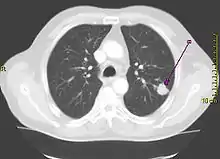

![]() Tumoare pulmonară (marcată cu săgeată) vizibilă la radiografia toracică | |

Diagnostic

Efectuarea unei radiografii toracice reprezintă unul dintre primii pași necesari pentru a investiga dacă o persoană prezintă simptome care pot sugera prezența cancerului pulmonar. Această radiografie poate arăta o masă evidentă, o extindere a mediastinului (sugerează răspândirea în nodulii limfatici), atelectazie (colabare), consolidare (pneumonie) sau revărsat pleural.[5] Imagistica prin computer tomograf este de obicei folosită pentru a oferi mai multe informații cu privire la tipul și gradul de extindere al bolii. Bronhoscopia sau biopsia ghidată CT este adesea folosită pentru a preleva mostre din tumoare pentru histopatologie.[13]

Cancerul pulmonar se prezintă, de cele mai multe ori, ca un nodul pulmonar solitar în cadrul unei radiografii toracice. Cu toate acestea, diagnosticul diferențial este extins. Multe alte boli pot să prezinte aceleași simptome, inclusiv tuberculoza, infecțiile fungice, cancerul metastatic sau pneumonia organizată. Printre cauzele mai puțin comune ale nodulului pulmonar solitar se numără hamartomul, chisturile bronhogenice, adenoamele, malformația arterio-venoasă, sechestrarea pulmonară, nodulii reumatoizi, granulomatoza Wegener sau limfomul.[45] Cancerul pulmonar poate fi, de asemenea, descoperit incidental, sub forma unui nodul pulmonar solitar la nivelul unei radiografii toracice sau tomografii computerizate realizate din alte motive.[46] Diagnosticul definitiv de cancer pulmonar are la bază examinarea histologică a țesutului suspectat în context clinic și radiologic.[4]